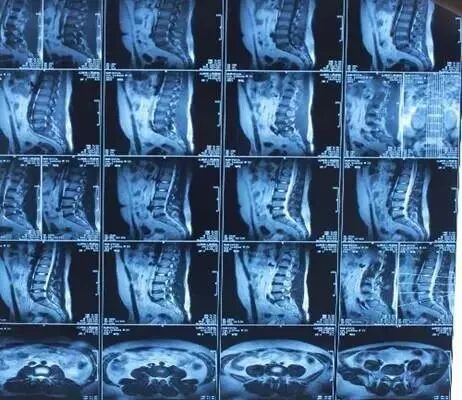

核磁共振机使用较强大的磁场,使人体中所有水分子磁场的磁力线方向一致,这时磁共振机的磁场突然消失,身体中水分子的磁力线方向,突然恢复到原来随意排列的状态。反复多次施加磁场又突然消失,核磁共振机会得到充分的数据并运算后成像。

磁共振可以检查的部位很多,包括脑部、血管、肌肉、韧带、脊柱等等,但是建议在有症状或医生建议下做磁共振检查,正常的体检作为疾病的初期筛查,通常没有必要做磁共振。